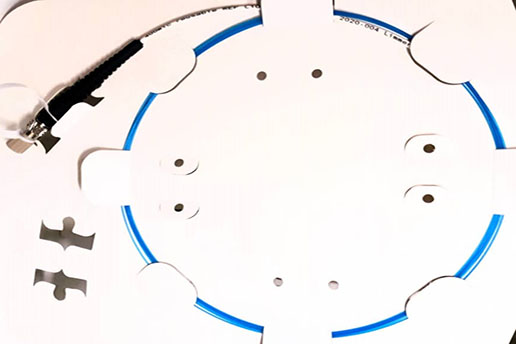

Reusable Polyimide Coated Single Ring Radial Fiber

A single ring radial fiber precisely covered by a dome shaped fused silica capillary tube protecting the radial tip during surgery and facilitates the fiber tip movement through veins. This cap also protects the fiber tip from carbonization and keeps the fiber efficiency for several surgeries. This probe can easily penetrate inside the veins, thanks for no sharp and brittle edge on the probe.

Properties |

Fiber type Loose Tube |

400 and 600um Colored Hytrel or without loose tube |

|

Fiber length |

2m |

|

Connector type |

SMA905 connector or HP-SMA905 |

|

Distal tip NA Sterilization |

Encapsulated angled tip 0.22 EtO-sterilized |

Application

Vascular, plastic, gynecological and ENT surgery

Hemorrhoids and fistulas

Optional features

- extension sleeve available in various colors

- Laser inscription possible

- Customer-optimized designs on request

- Various accessories available

Certifications & approvals: (In Progress)

Our production processes, devices and procedures is certified by ISO 13485 .

And Iran national medical device directorate (IMED)